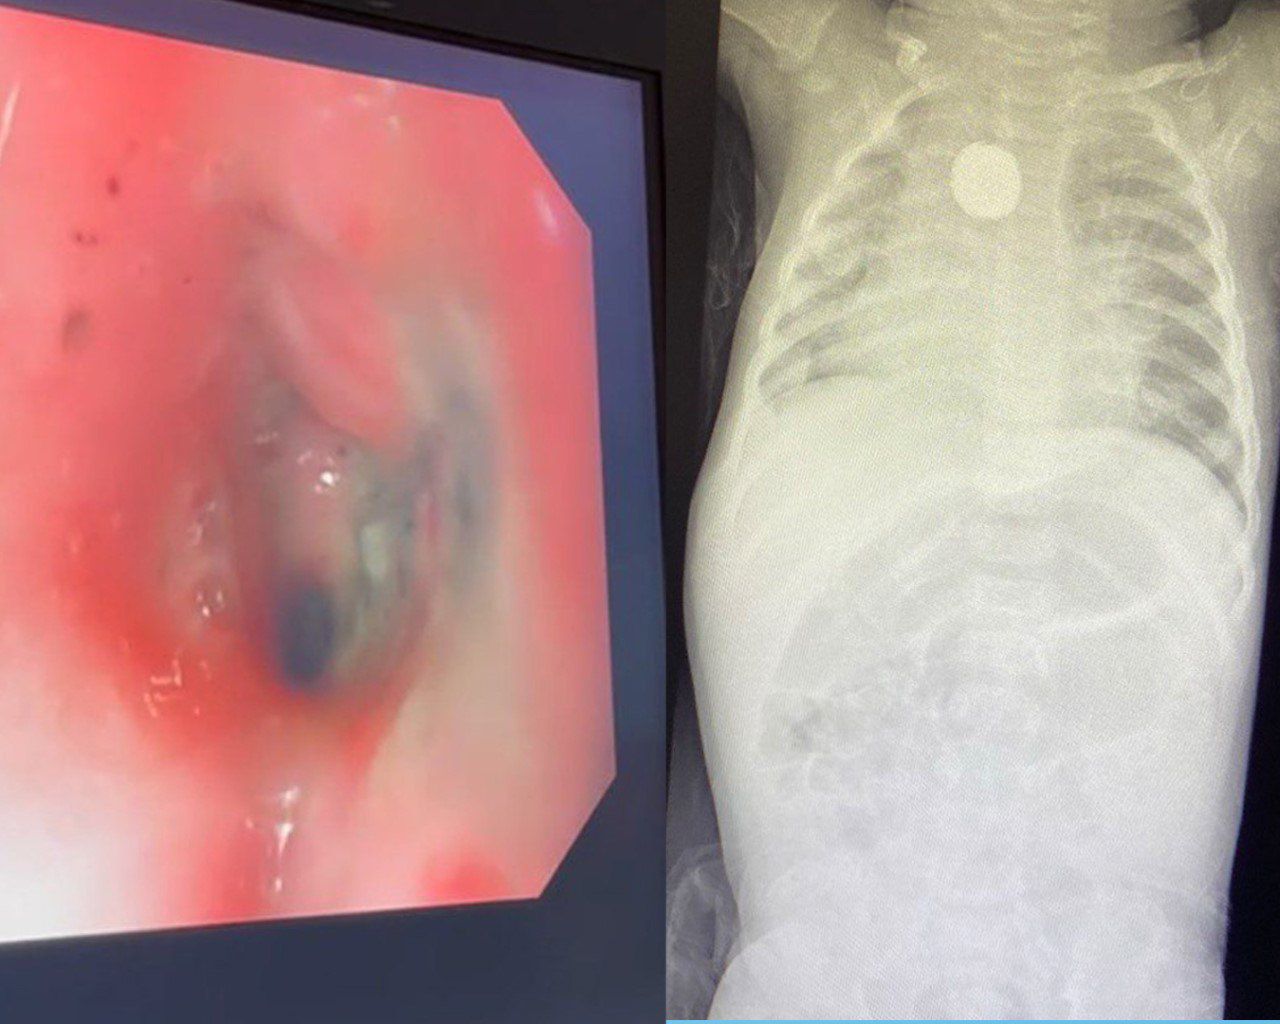

وأوضح تجمع مكة المكرمة الصحي، حضرت الطفلة إلى قسم الطوارئ كحالة إنقاذ حياة وهي تُعاني من التهاب متكرر في الحلق منذ شهر، ومع مضي الأيام أصبح البلع لديها صعب ولم تتمكن من البلع العادي منذ أكثر من خمسة عشر يوماً، وعلى الفور أجريت الفحوصات اللازمة حيث جرى اكتشاف جسم غريب مما استدعى التدخل الطبي العاجل لإنقاذ الطفلة، وتم تكوين ثلاث فرق طبية لاستخراج البطارية الحارقة دون حدوث مضاعفات، متمثلة في فريق قسم المناظير، وجراحة القلب والشرايين، وجراحة الأطفال، وتبين من خلال الأشعة المقطعية وجود الجسم الغريب على مقربة من شرايين القلب، مختفياً في جدار المريء مع الضغط على الحنجرة المجاورة.

وأضاف تبين وجود حروق داخل المريء مع تضيق المنطقة المتأثرة وعدم رؤية الجسم الغريب مبدئيا وبعد عدة محاولات اتضح وجوده ملتصقاً ومغطى بأغشية الجدار داخليا، مما أتاح إمكانية سحبه بالمنظار بسلام دون حدوث ثقب أو نزيف في المنطقة ذاتها، وجرى إدخال المنظار مرة أخرى والتأكد من عدم وجود ثقب أو تسرب هوائي داخل الصدر.